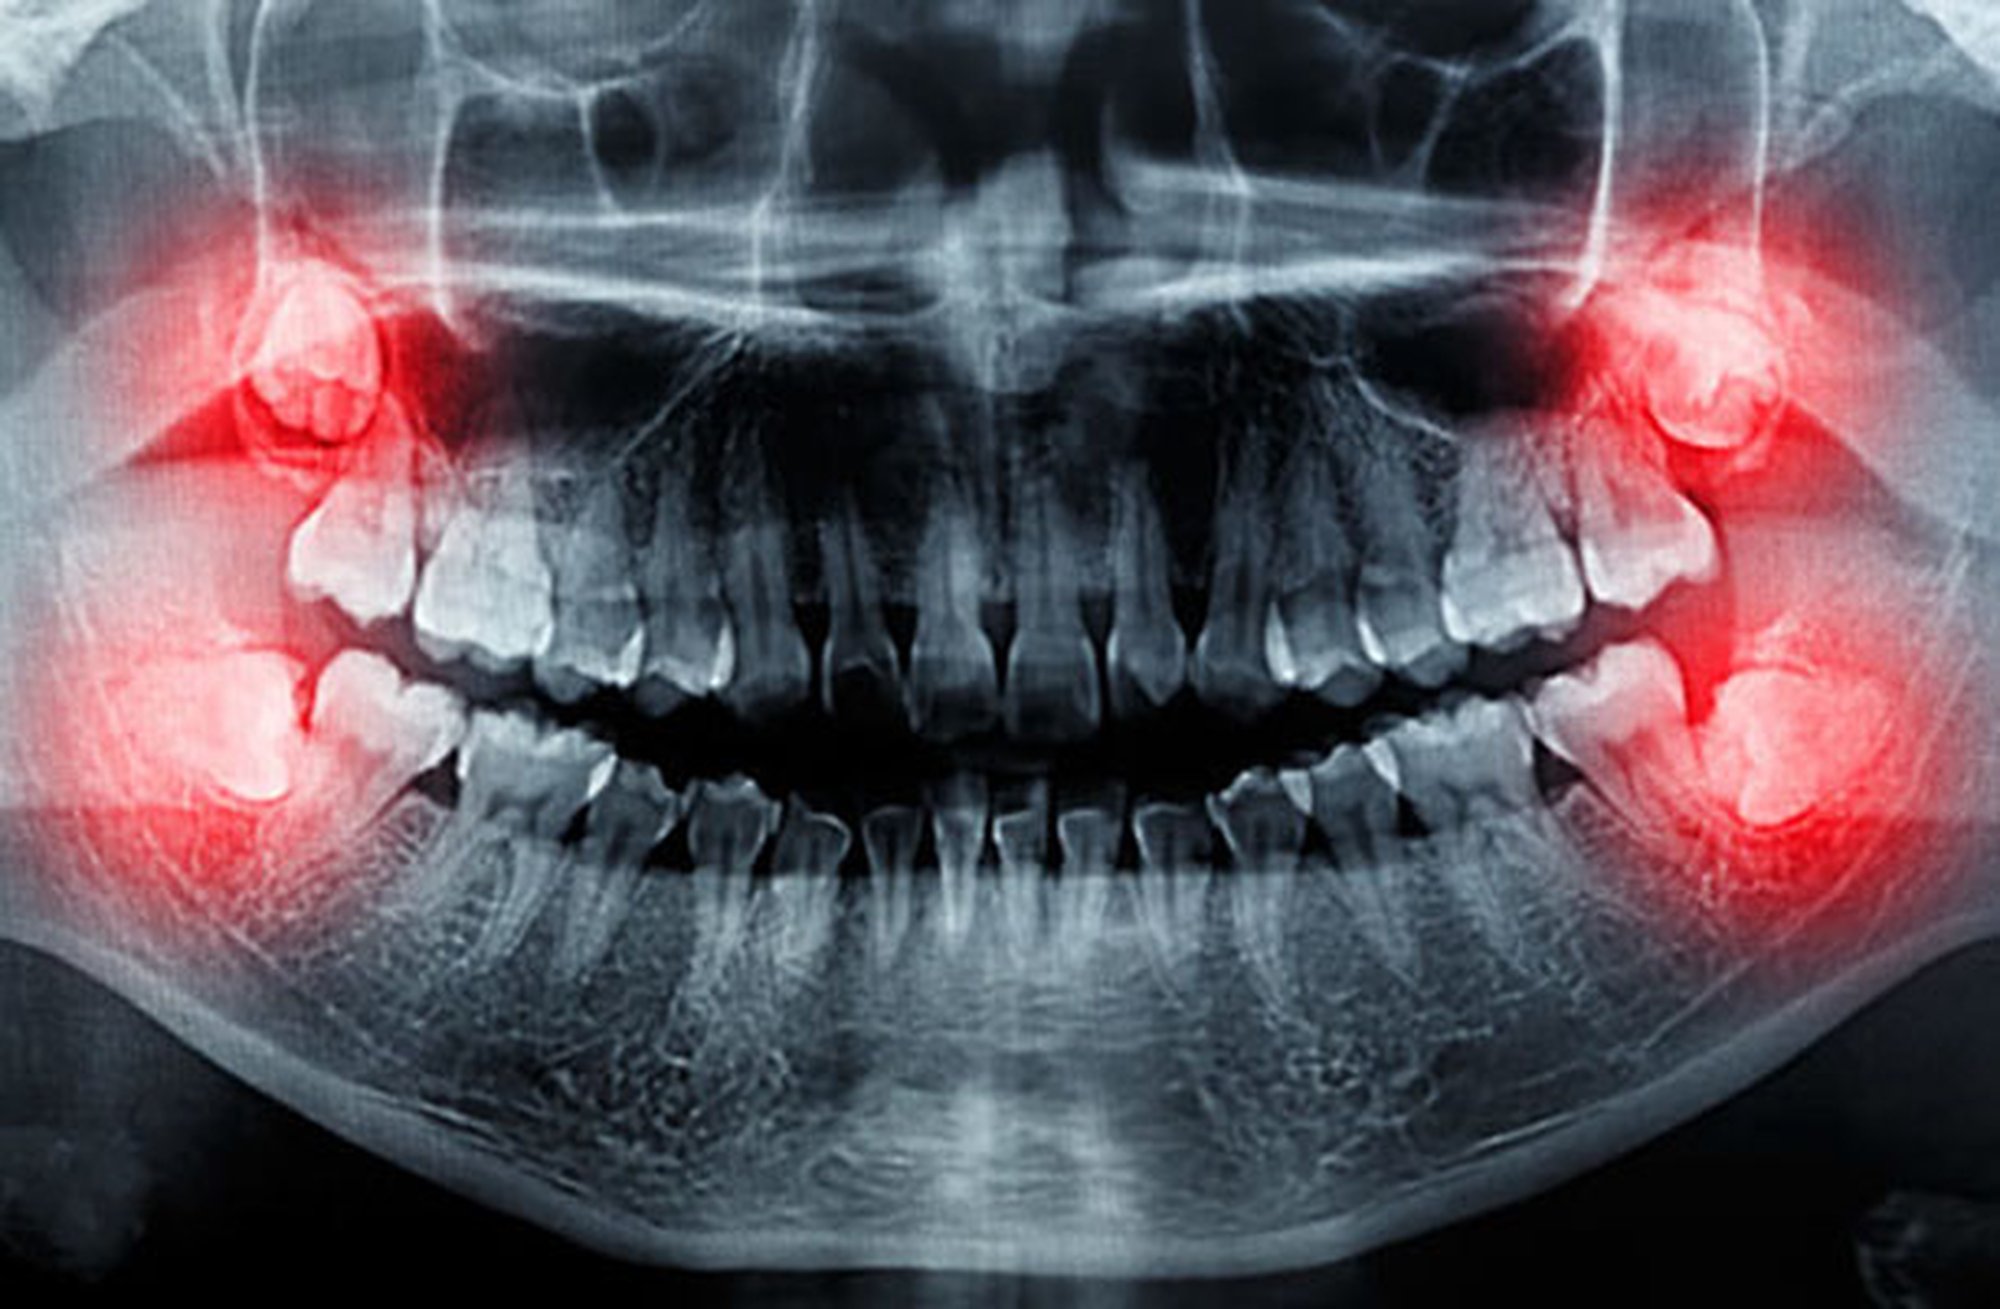

Tahminimce tıbbın ve dişçiliğin gelişmediği dönemlerde yirmilik dişlerin düzgün bir şekilde çekilmesi ve iltihap kapmaması o kadar da mümkün değildi. 17 yaşlarında çıkmaya başlayan gömülü kalma çürüme kist oluşumu, çene kilitlenmesi, kronik enfeksiyon, dişlerde baskı ve çarpıklığa neden olabilecek bir yapı türün devamlılığı için de bir sorun olmalı